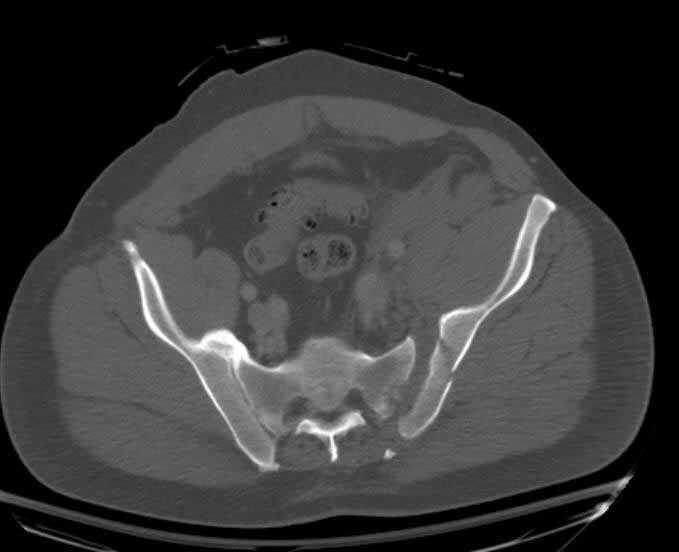

Post trauma day ten patient's xray shows failure of posterior construct. Plan was to perform revision orif once soft tissues resolve considerably for full anrterior fixation and posterior fixation. However, while Im away for holiday (on Post trauma day 15), pt is developing septic clinical appearance, and trauma suspects pelvic abcess near symphysis and performs I and D - finds nothing but no primary closure performed. Posterior tissues/incision continue to look healthy. Now is post trauma day 17, pt is still tubed/on dopamine/and wbc still elevated, anterior incision still packed open.

On 11/29 took patient back to OR and explored both his anterior and posterior wounds, removed loose illiosacral screws. Left behind the screws fixing illiac crescent. Found anterior wound clean and closed it. Found posterior wound with moderate seroma and some adjacent fat necrosis. Thus far, cultures negative, but not kidding myself on that fact. Wound VAC placed and going back tomorrow to reexamine wound and may close it or re-VAC one more time. Fixator remains in place.

It appears from post-failure CT scan that the path of the more cephalad IS screw may be helpful to place a longer screw to engage opposite illiac wing as an option, or just anterior SI plates. not likely to do this tomorrow as he remains in a fragile clinical situation regarding his pulmonary status, and profound edema/induration around his pelvis/abdomen and thighs.